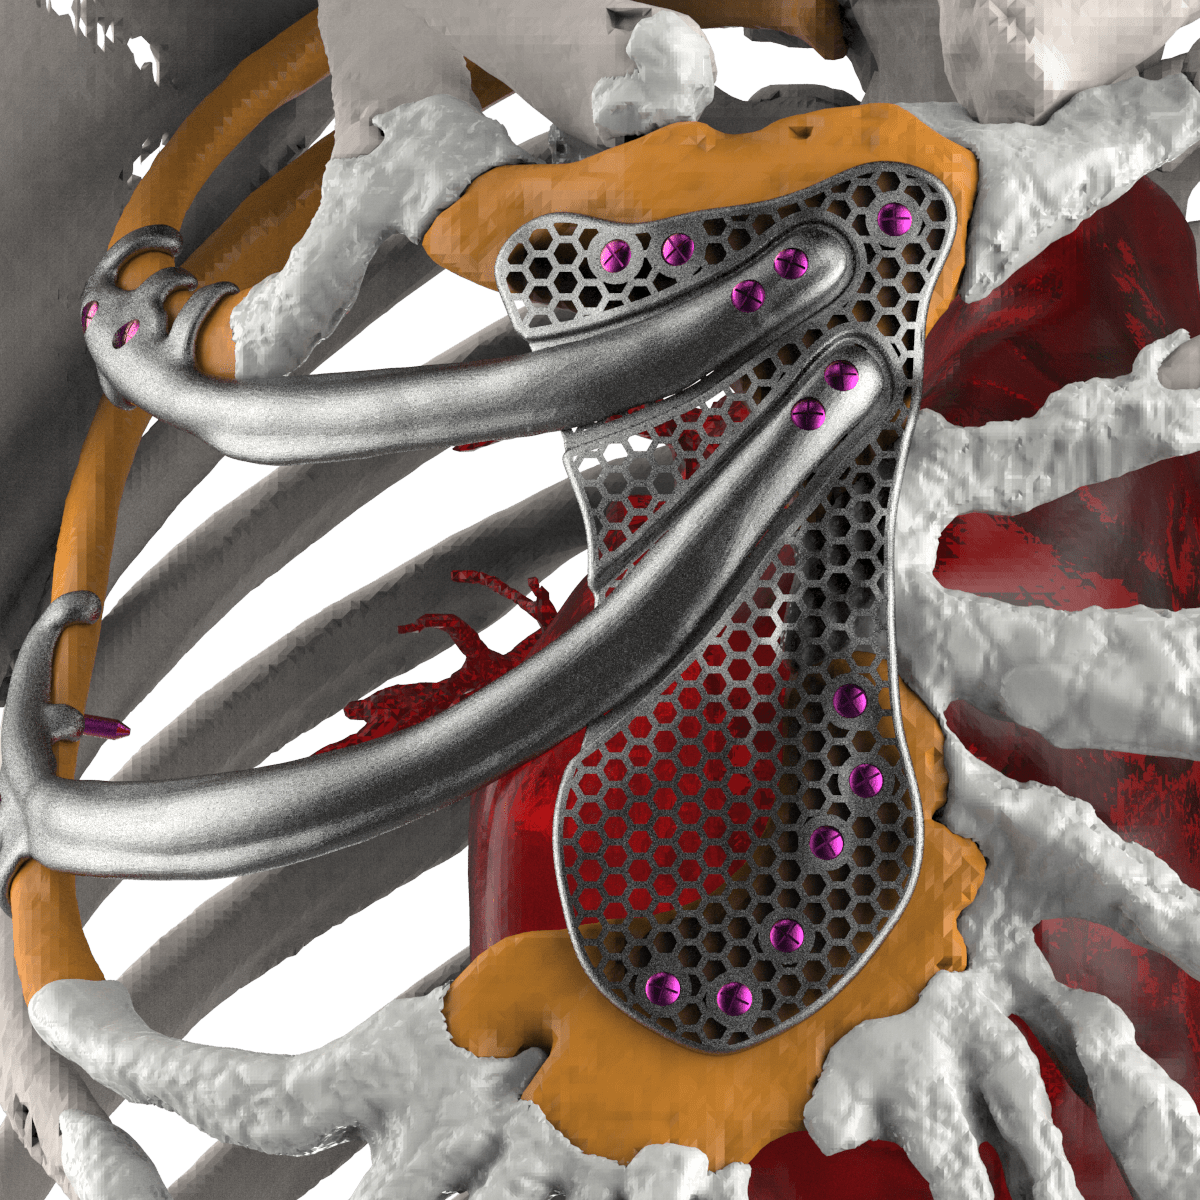

Patient-specific equipment (such as hearing aids) and implants (such as artificial limbs, cranial plates, and even heart valves) are increasingly turning to 3D printing for rapid modification and accelerated development.

There are design advantages too: 3D printed silicone heart valves have the perfect match that rigid, commonly designed heart valves simply can’t. For implants such as titanium artificial joints or cranial plates, the services of 3D printing companies can produce intricate and porous surfaces that make patients’ bodies less likely to resist implants.